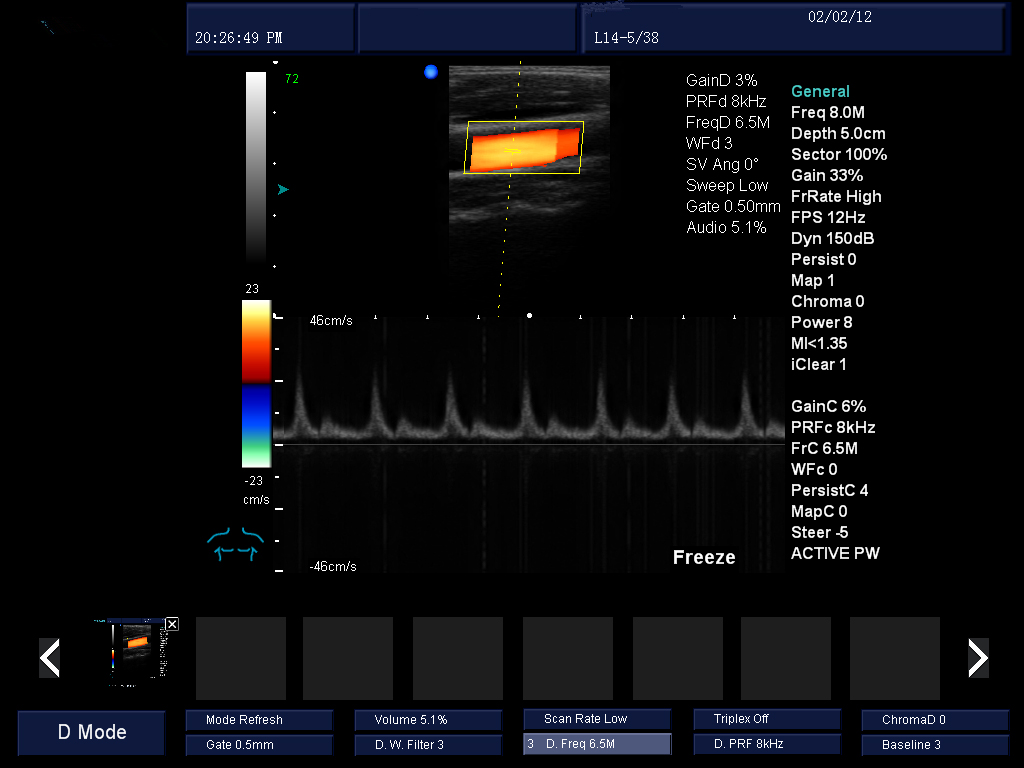

動(dòng)態(tài)實(shí)時(shí)血管成像:通過精確的多普勒回聲信號(hào)自動(dòng)識(shí)別處理,減少血管壁和血流的多普勒信號(hào)回疊,使血管內(nèi)血液和血管多普勒成像顯示更清晰。